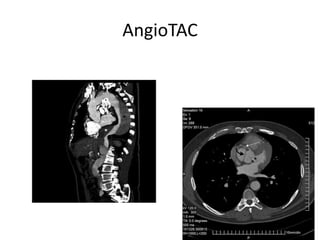

AngioTAC

AngioTAC 3d